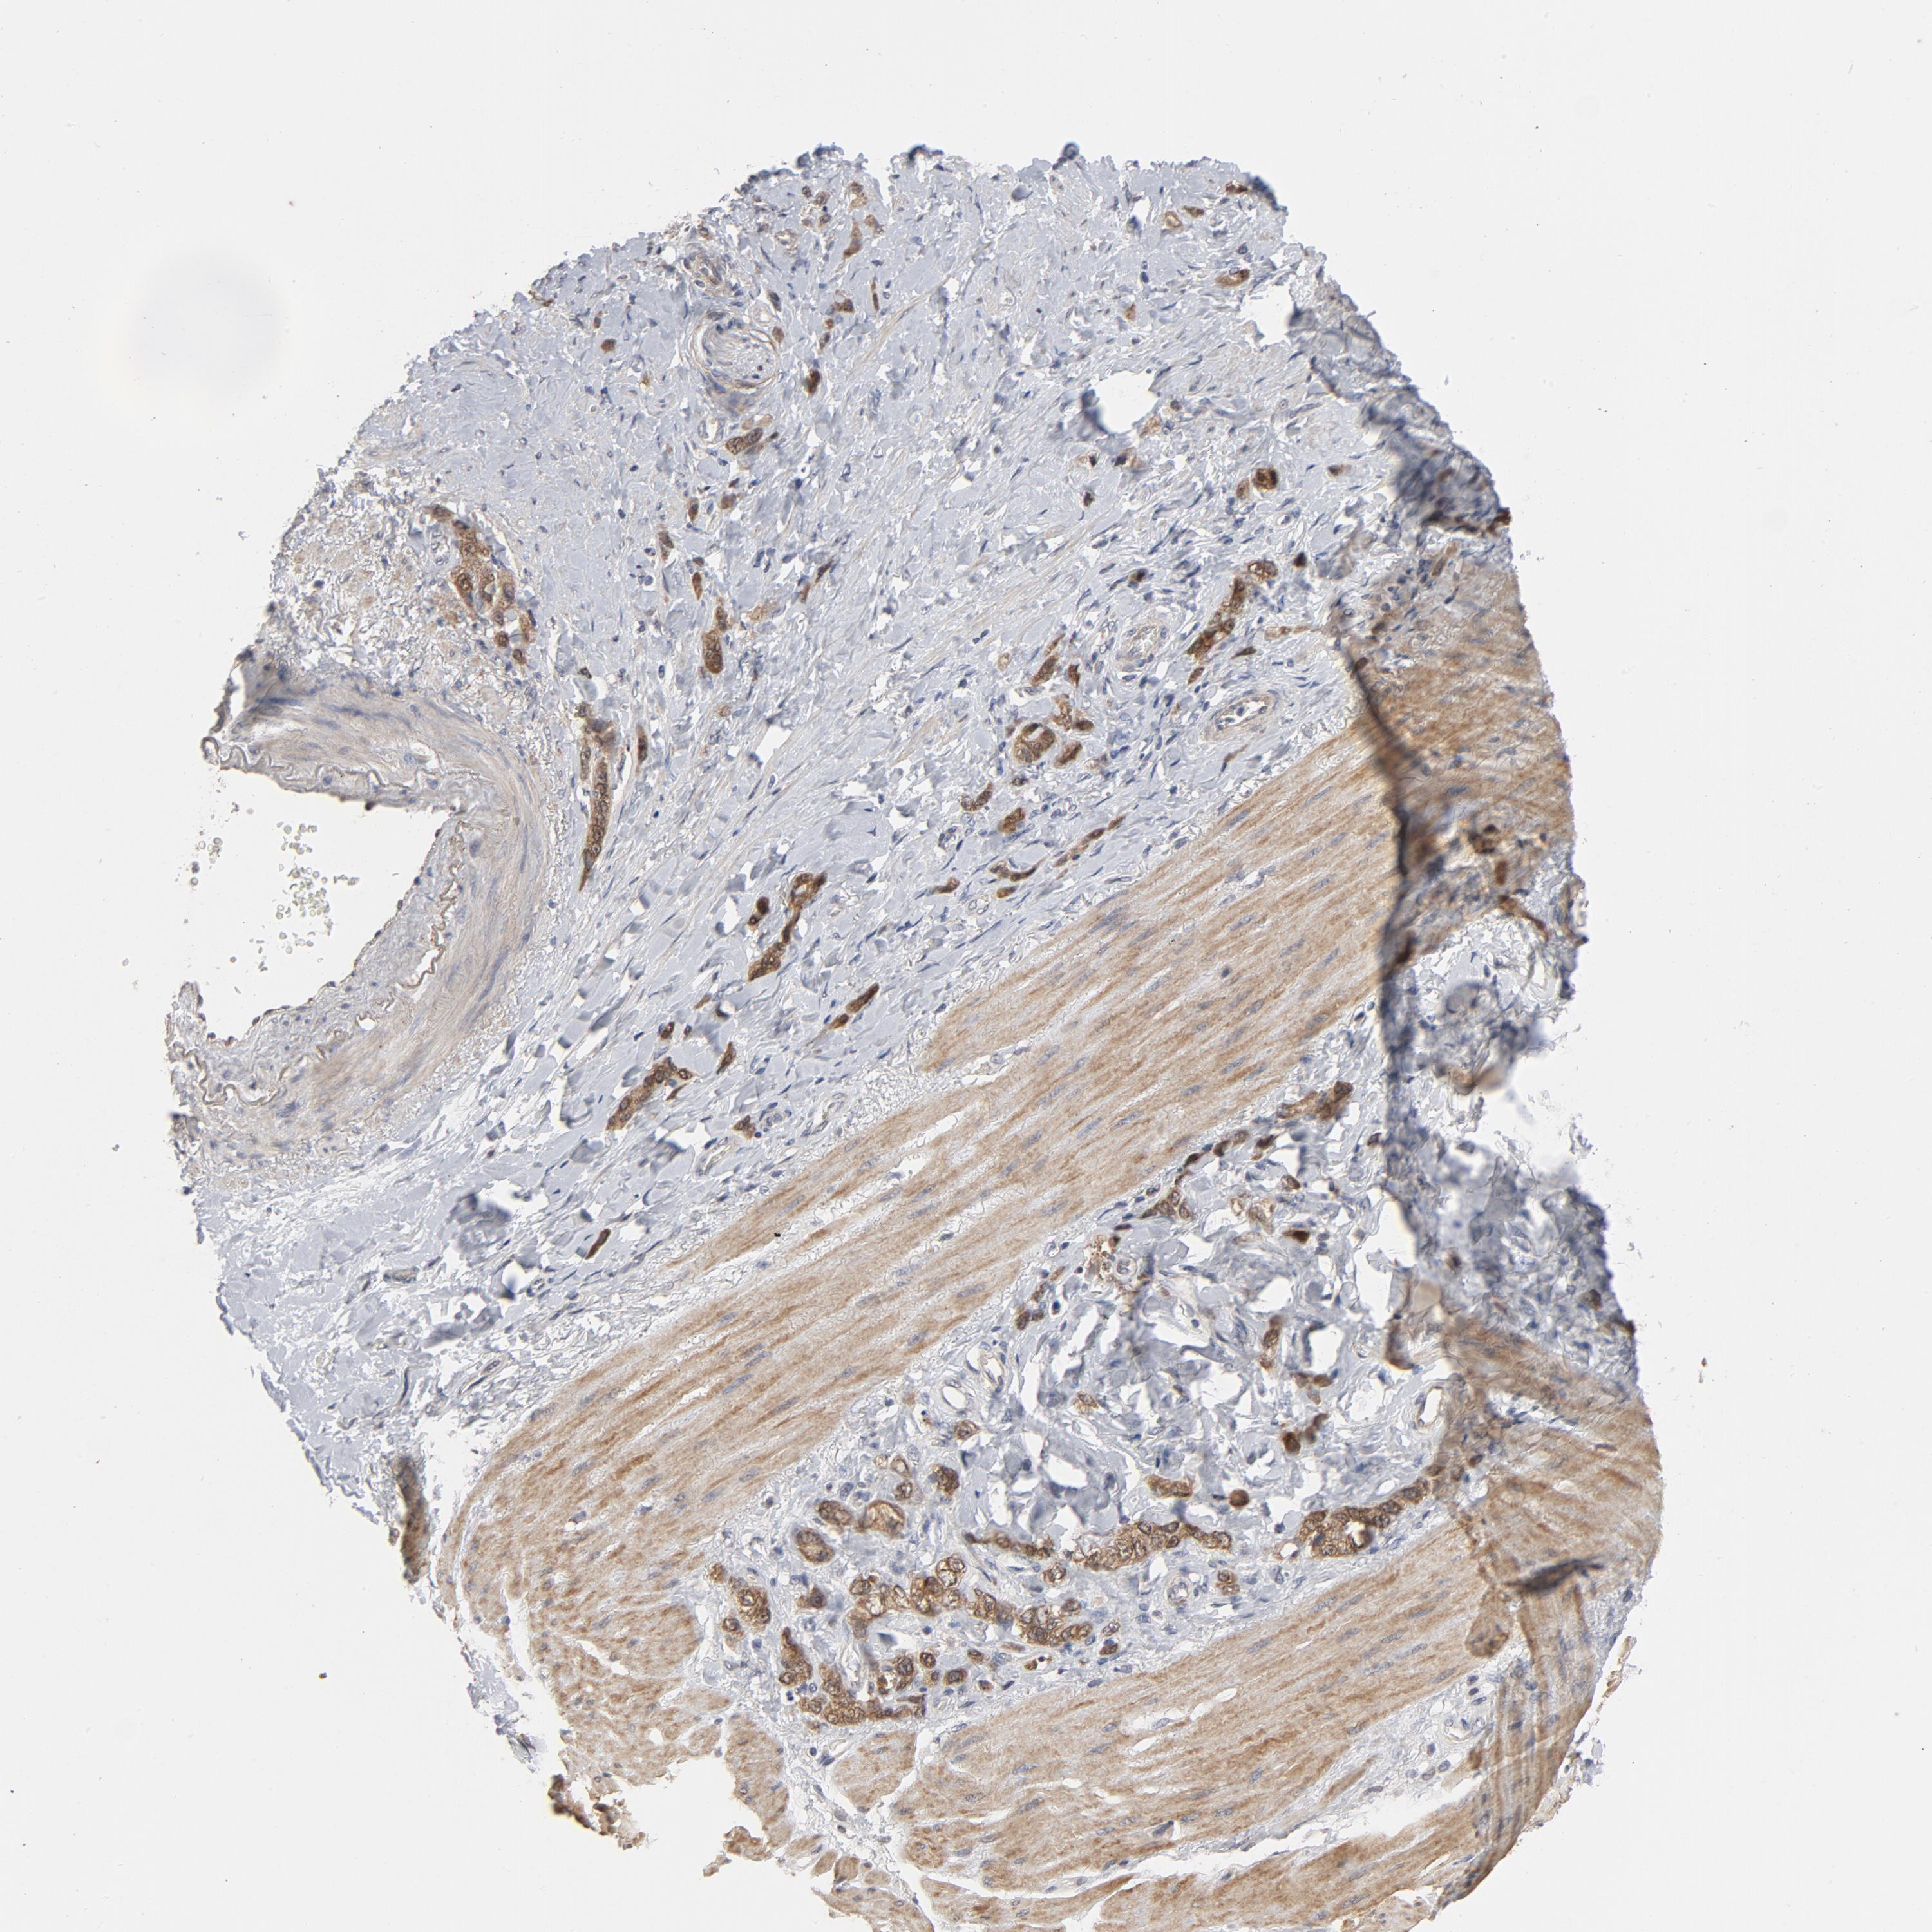

STOMACH CANCER - Protein expressioni

A mouse-over function shows sample information and annotation data. Click on an image to view it in a full screen mode. Samples can be filtered based on level of antibody staining by selecting one or several of the following categories: high, medium, low and not detected. The assay and annotation is described here.

Note that samples used for immunohistochemistry by the Human Protein Atlas do not correspond to samples in the TCGA dataset.

Antibody stainingi

Antibody staining in the annotated cell types in the current human tissue is reported as not detected, low, medium, or high, based on conventional immunohistochemistry profiling in selected tissues. This score is based on the combination of the staining intensity and fraction of stained cells.

Each image is clickable and will lead to virtual microscopy that enables deeper exploration of all samples and also displays staining intensity scores, fraction scores and subcellular localization as well as patient and tissue information for each sample.

Antibody HPA048630

Antibody HPA061142

Antibody CAB004026

Staining

High

Medium

Low

Not detected

Intensity

Strong

Moderate

Weak

Negative

Quantity

>75%

75%-25%

<25%

None

Location

Nuclear

Cytoplasmic/membranous

Cytoplasmic/membranous,nuclear

Adenocarcinoma, NOS

Adenocarcinoma, High grade